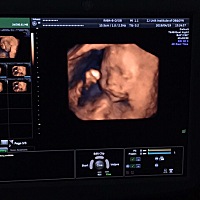

今天22周了哈🐷佩奇呵呵😄